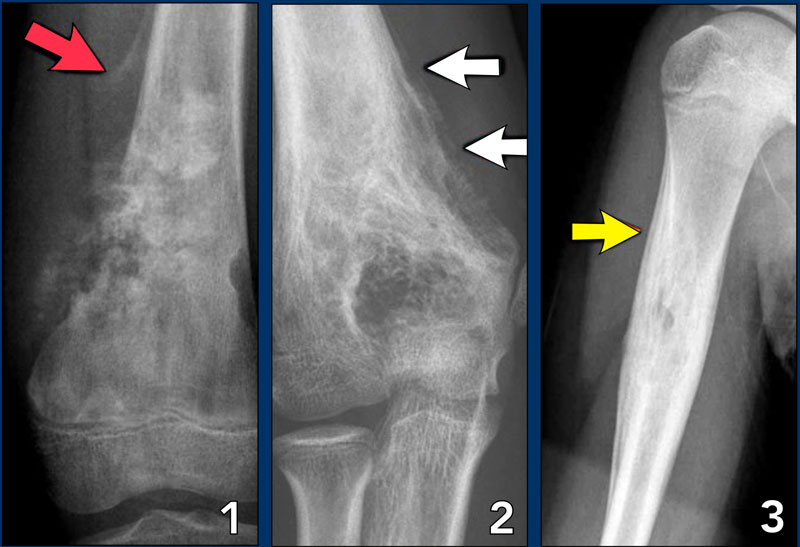

(A, B) The spiculated pattern of the periosteal reaction and Codman's Periosteal Reaction X Ray a periosteal reaction is the formation of new bone in response to injury or other stimuli of the periosteum surrounding the bone. learn about the different types and causes of periosteal reaction, a membrane that covers the majority of. localized periosteal reaction develops that is indistinguishable from psoriatic arthritis but more commonly affects the lower extremities (such.. Periosteal Reaction X Ray.

Radiography of right knee (3rd case) the periosteal reaction at the Periosteal Reaction X Ray localized periosteal reaction develops that is indistinguishable from psoriatic arthritis but more commonly affects the lower extremities (such. periosteal reaction results when cortical bone reacts to one of many possible insults. periosteal reaction refers to the elevation of periosteum from cortical bone and the subsequent deposition of new. the periosteum is a membrane several cell layers. Periosteal Reaction X Ray.